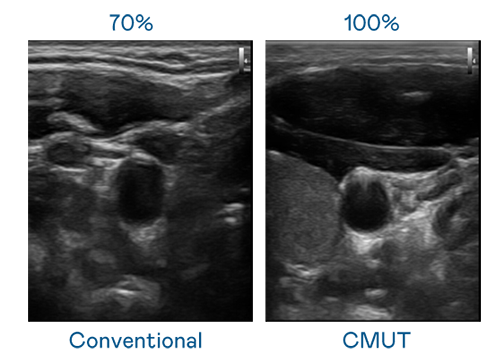

CMUT 技术是一种用电容式微机电元件来产生超音波讯号的技术。与传统 PZT 压电式技术相比,CMUT 频宽增加 30%,更宽频的超音波讯号让影像解析度大幅提升,是实现高影像品质医疗超音波扫描、促进精准医疗发展的关键技术。

大频宽带来超清晰影像

超音波影像的解析度高低,首先取决于探头能发出的讯号频宽。AG电子 CMUT 可提供高清晰的超音波讯号,提供高频宽、高灵敏度、影像纹理细节更高的超音波影像,协助医护人员缩短影像判读时间及利用精准的医疗影像进行诊断。